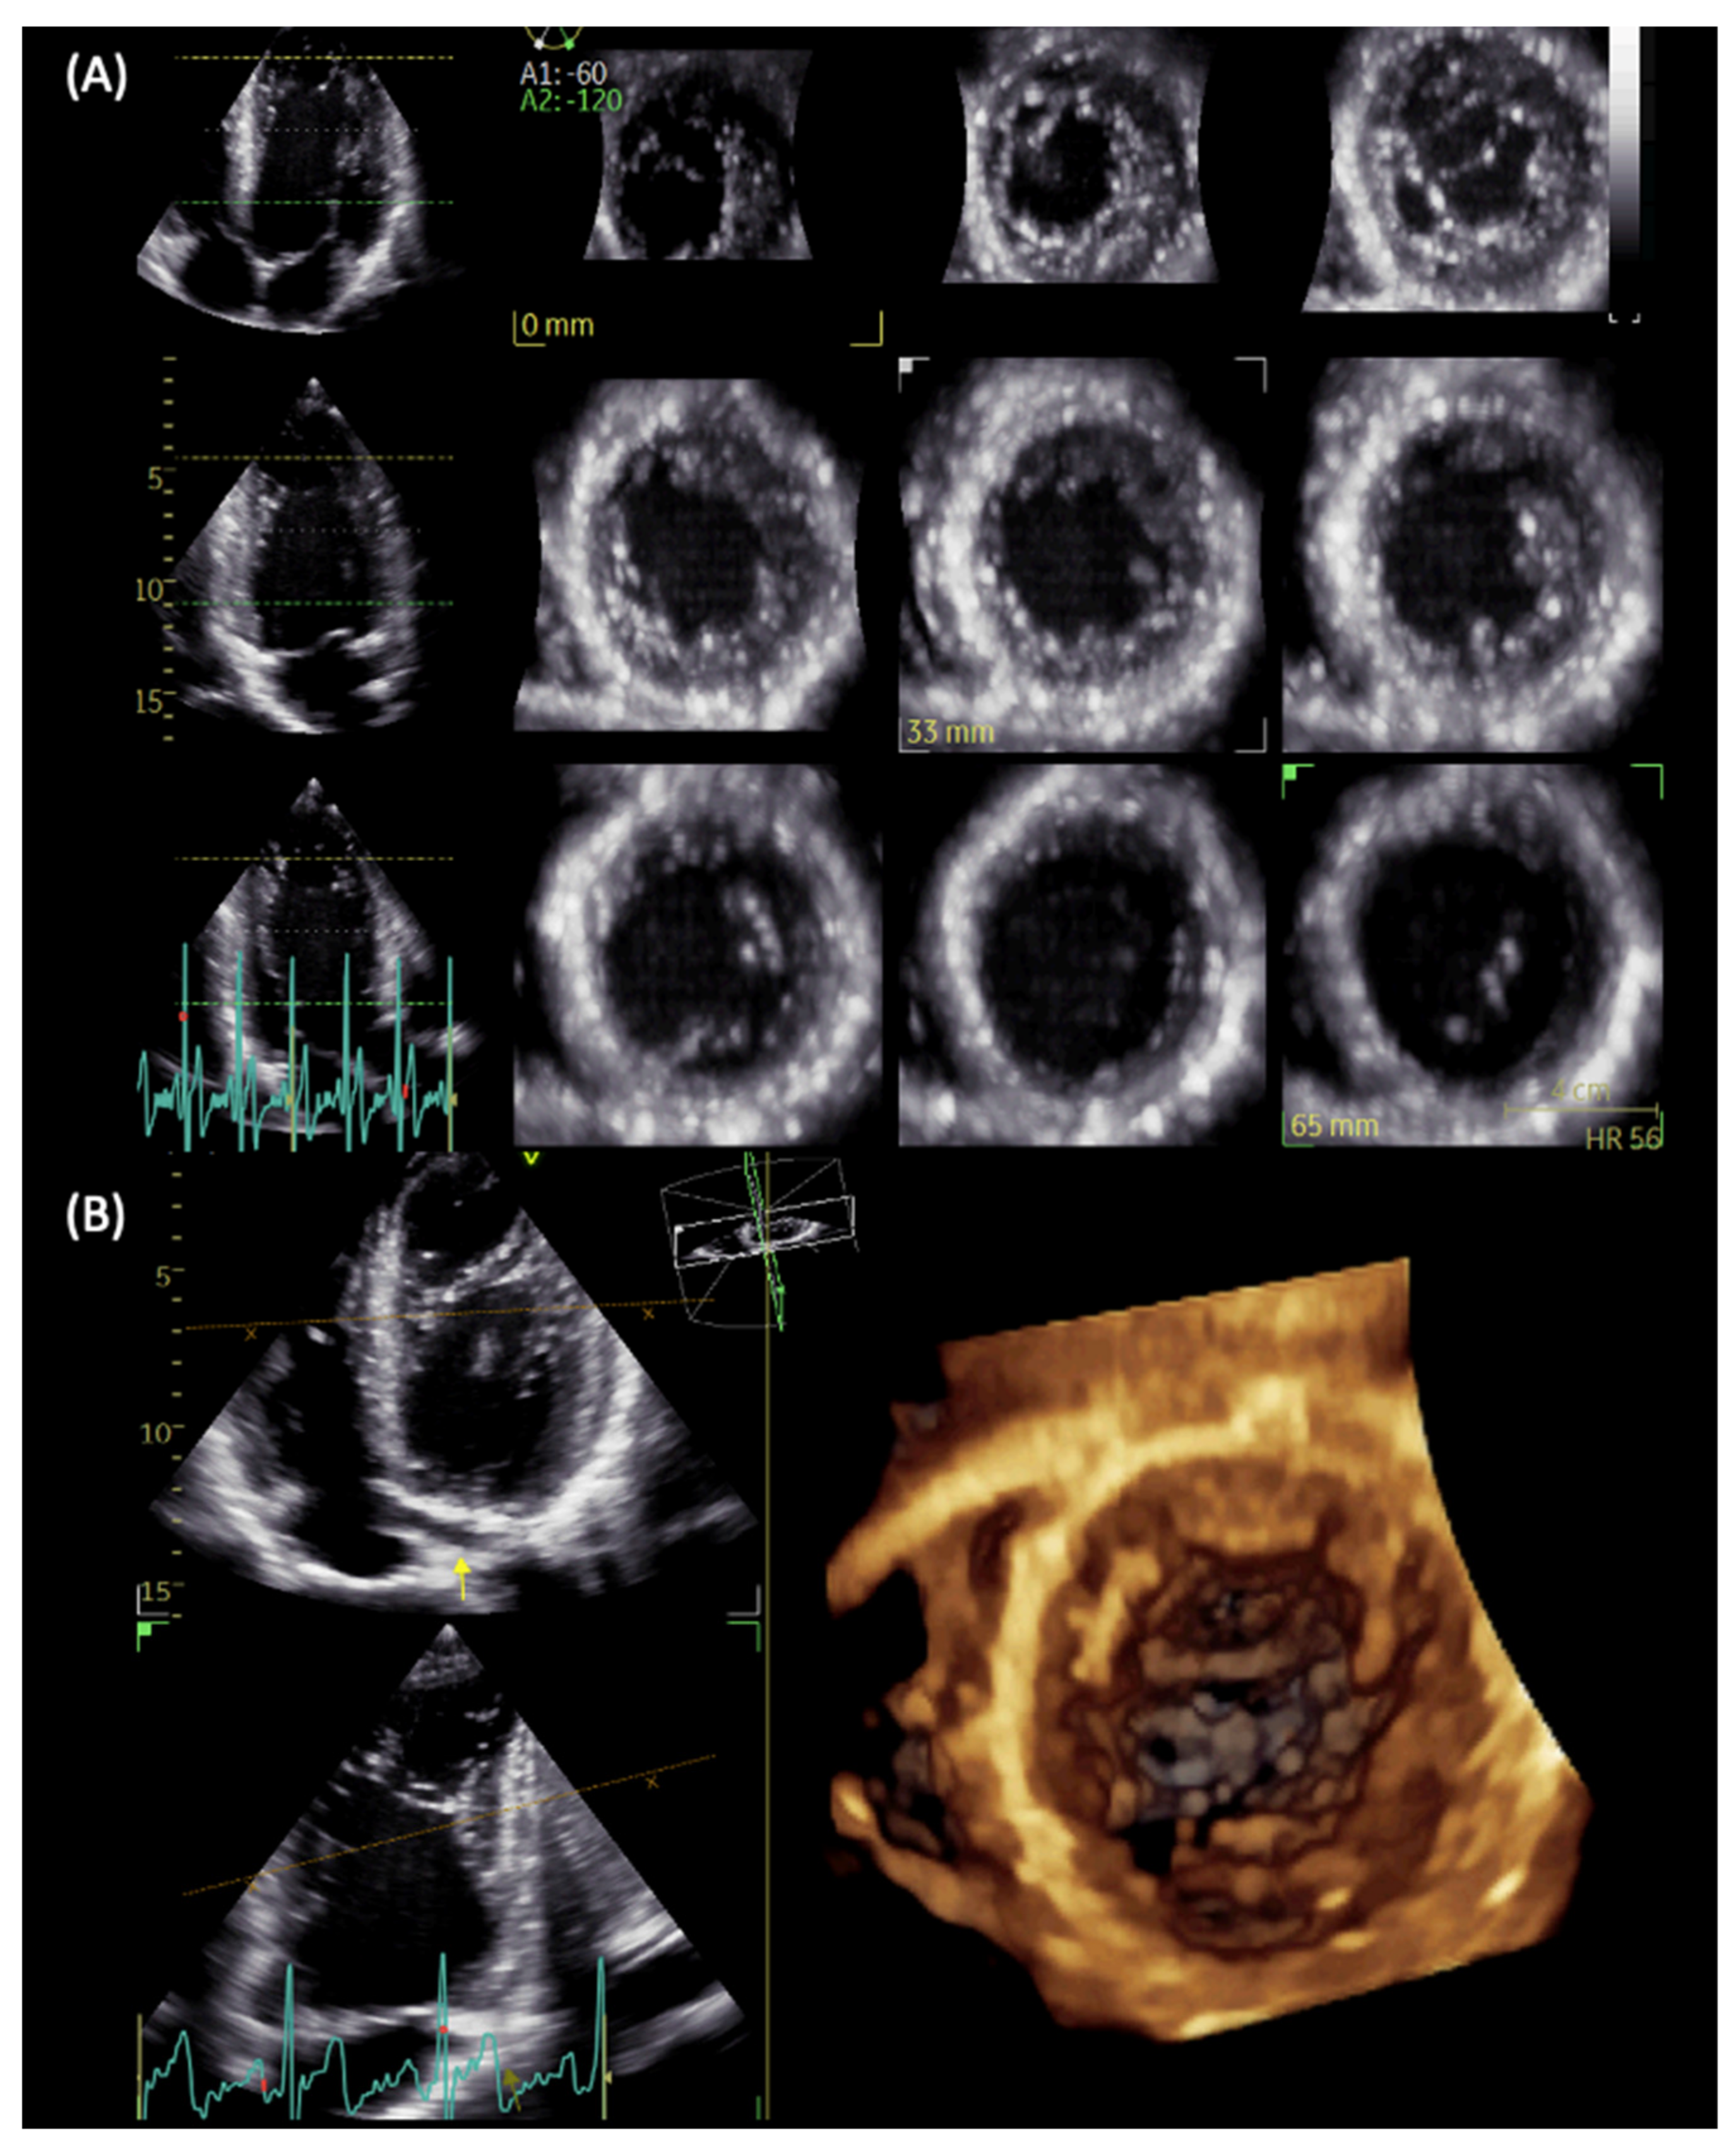

Figure 3.

LVNC in a patient with repaired aortic coarctation. Three-dimensional echocardiography with full-volume acquisition allows the better visualization of multiple apical intertrabecular recesses with multislice (A) and 3D reconstructions (B).